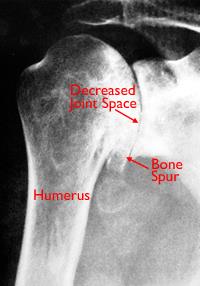

X-ray and illustration showing osteoarthritis of the shoulder

An X-ray and illustration showing damaged cartilage in the glenohumeral joint.

Illustration reproduced and modified with permission from JF Sarwark, ed: Essentials of Musculoskeletal Care, ed 4. Rosemont, IL, American Academy of Orthopaedic Surgeons, 2010.

X-rays are imaging tests that create detailed pictures of dense structures, like bone. They can help distinguish among various forms of arthritis.

X-rays of an arthritic shoulder will show:

• A narrowing of the joint space

• Changes in the bone

• The formation of bone spurs (osteophytes)

X-ray of severe osteoarthritis of the glenohumeral joint

This X-ray shows severe osteoarthritis of the glenohumeral joint.

Reproduced with permission from Crosby LA (ed): Total Shoulder Arthoplasty. Rosemont, IL, American Academy of Orthopaedic Surgeons, 2000, p 18.